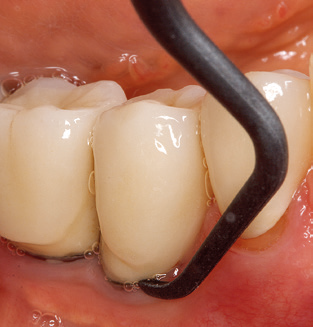

The current working concept for SPT

Fig. 4: Flexible probes with millimetre markings are recommended for the probing of dental implants (e.g. Colorvue Kit PCV11KIT6, Hu­Friedy). – Fig. 5a and b: A straight working tip (1P, W&H Dentalwerk Bürmoos GmbH) is a suitable instrument for use on all natural teeth. – Fig. 6: Curved working tips (3Pr/3Pl, W&H Dentalwerk Bürmoos GmbH) lend themselves to the processing of difficult-to-reach areas of the tooth and root surfaces (e.g. furcations). – Fig. 7: The tapered, hexagonal implant cleaning tip (1I, W&H Dentalwerk Bürmoos GmbH) permits atraumatic and efficient cleaning of the crown and abutment surfaces. – Fig. 8: Titanium and carbon curettes are suitable instruments for the manual cleaning of the implant surfaces.

Of course, the use of instruments for mechanical removal of the biofilm is a central component of SPT and thus of primary significance. Consequently, the SPT workflow comprises both supragingival and subgingival cleaning. In our concept, a combination of hand instruments and machine cleaning has proven advantageous. A number of options are available for the mechanical procedures: sonic devices, ultrasonic devices and powder jet devices.

Good illumination of the working field facilitates the process considerably. The system used by the authors achieves this thanks to a 5x LED ring integrated in the handpiece. Naturally, a range of working tips for different indications is also offered. A straight, universally employable tip is the basic instrument required for machine cleaning of natural teeth (Fig. 5a and b). Curved tips, which allow access to exposed furcations, are also available for hard-to-reach areas in the posterior region (Fig. 6).